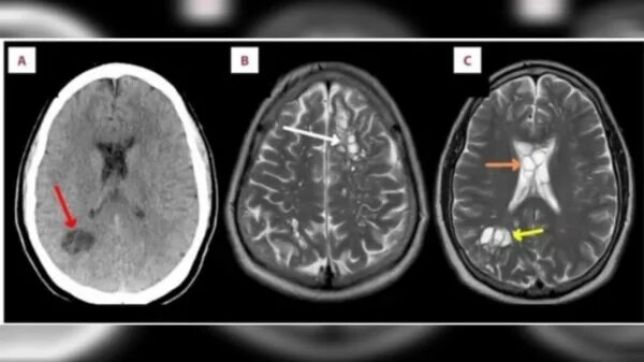

Os médicos encontraram larvas de tênia alojadas no cérebro do paciente, de acordo com o relato de caso e imagens publicadas no American Journal of Case Reports. O paciente vinha se queixando de dores de cabeça insuportáveis há pelo menos quatro meses.

Após o diagnóstico, o americano fez o tratamento à base de dexametasona, esteroide frequentemente usado para tratar alergias, e de albendazol, usado para conter parasitas. De acordo com os médicos, as lesões no cérebro diminuíram e as dores de cabeça melhoraram após o tratamento.